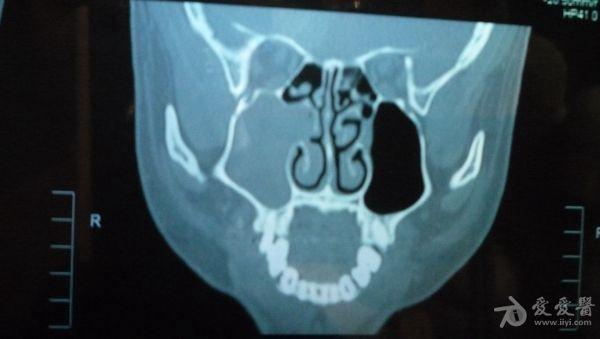

CT结果是右侧上颌窦及部分筛窦窦腔内见稍高密度影填充,CT值约21U,窦壁骨质未见破坏征象;鼻腔后部亦见少量稍高密度影填充;左侧上颌窦、筛窦及蝶窦、额窦未见明显异常。CT图片见附件。医生说我的右边鼻窦都被软组织堵死了,必须要做手术清楚后再做病理分析看是良性还是恶性。

想请问下医生:CT图片上右边的上颌窦内的稍高密度影,是软组织还是液体的几率大些呢